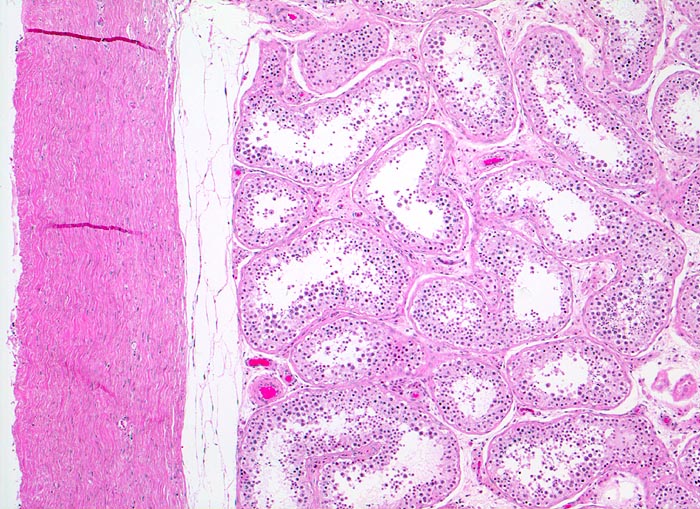

PathoPic ID 4123 - normales Hodenparenchym und Tunica albuginea

normales Hodenparenchym und Tunica albuginea

Normalbefund

Hoden

Genitalorgane, männlich

Unauffälliges Hodenparenchym mit ausreifender Spermiogenese. Links im Bild die dichte kollagenfasrige Tunica albuginea.

Histologie

50

43

männlich